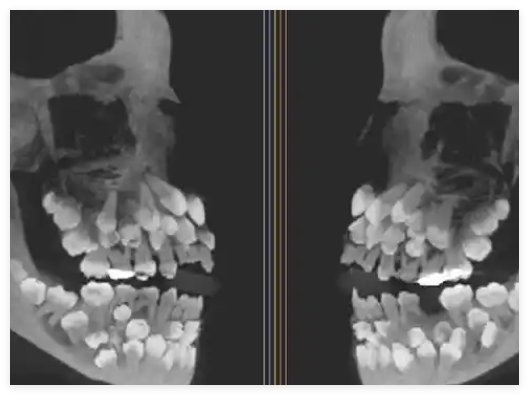

巴西米納斯吉拉斯州一名11歲女孩被發(fā)現(xiàn)口中竟有多達(dá)81顆牙齒,引發(fā)醫(yī)學(xué)界震動(dòng)。該罕見病例由巴西聯(lián)邦大學(xué)Juiz de Fora的醫(yī)生團(tuán)隊(duì)記錄,并于近日發(fā)表在《美國(guó)正畸與頜面外科雜志》上。

女孩原本只是前往牙科檢查,打算拔除殘留的乳牙,X光檢查卻發(fā)現(xiàn)她不僅有18顆乳牙和32顆恒牙,還額外長(zhǎng)出了31顆“超生牙”,屬極罕見的“多重超數(shù)牙”病例。

通常此類患者僅多出少量牙齒,而這名女孩卻未攜帶任何已知相關(guān)遺傳綜合征,令人困惑。

醫(yī)生通過(guò)CT掃描及染色體檢測(cè),發(fā)現(xiàn)其第9號(hào)染色體存在一處罕見變異,但目前尚無(wú)法確認(rèn)該變異是否直接導(dǎo)致牙齒異常。